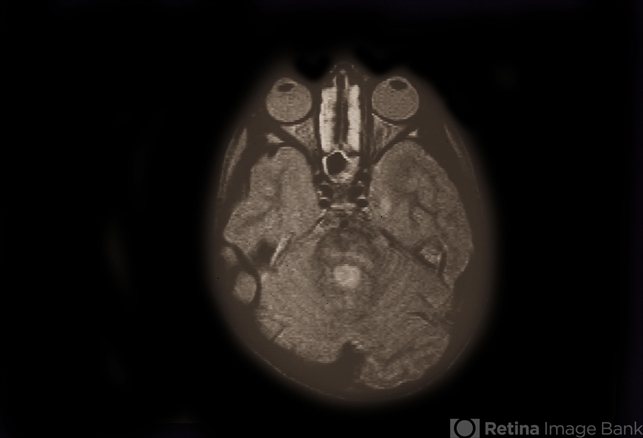

- Rhabdomyosarcoma R Orbit

- Condition/keywords

- rhabdomyosarcoma

- Four year old patient. CMC patient; embryonal rhabdo; CT, MRI, Clinical, and histology photos.